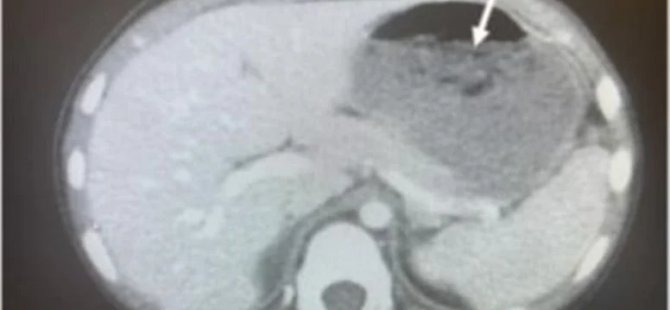

Ohio’da karın ağrısı, mide krampı ve ishal şikayetiyle hastaneye kaldırılan 5 yaşındaki çocuk bilim dünyasını şaşkına çevirdi. İsmi açıklanmayan çocuğu inceleyen doktorlar, röntgen sonuçlarını görünce adeta neye uğradıklarını şaşırdı.

Tıp literatürüne giren ve ABD başta olmak üzere uluslararası medya kuruluşlarında da geniş yer alan olayda röntgen sonuçlarını gören bilim insanları çocuğun midesinde bir öbek tespit etti. Daha detaylı inceleme yapılınca da bu büyük öbeğin çiğnenmiş sakız olduğu öğrenildi.

Doktorlar, detaylı inceleme sonucunda çocuğun midesinde sakız öbeği keşfetti.

Çocuğa ve ebeveynlerine sorular soran doktorlar, küçük çocuğun anne ve babasına haber vermeden 40 şekersiz sakız çiğnediği ve bunları daha sonra yuttuğunu öğrendi.

Tıp dergisi JEM’de yayınlanan raporda, çocuğun boğazına metal bir tüp sokarak midesindeki sakızın toplandığı da belirtildi. Bu işlemi birçok kez tekrarlayarak yapan doktorlar, çocuğun boğazında bir ağrı meydana geldiğini de duyurdu. Bilim insanları ebeveynleri uyararak, “Çocuklarınızın ne yediğine dikkat edin. Yanlışlıkla bir sakız yutmak başka bir şey, fakat birçok sakız yutmak ise tehlikeli bir durum” dedi.